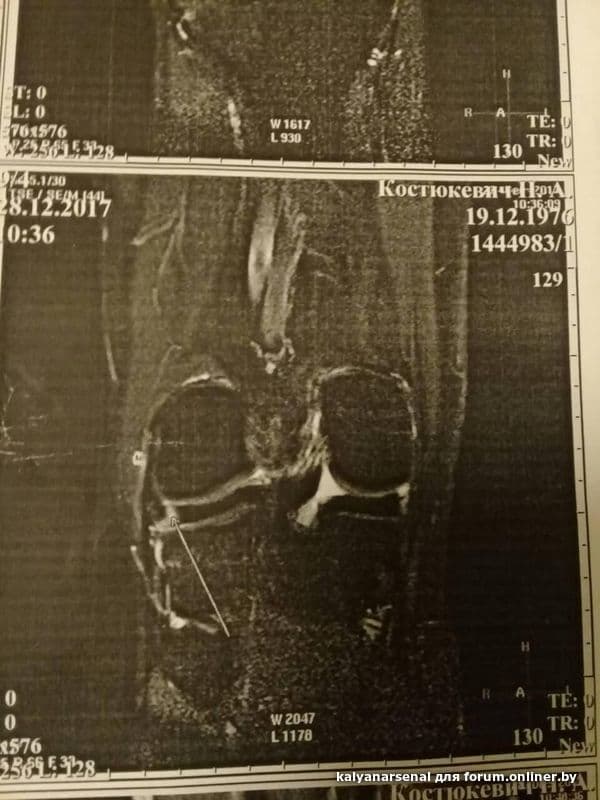

Здравствуйте,уважаемые форумчане и Дмитрий Святославович! Меня зовут Николай,мне 41год.

В общем,такая история.Всю жизнь занимался футболом, непрофессионально. И вот на последней игре выпрыгиваю я вверх за мячом,приземляюсь на одну прямую правую ногу-острая боль,полежал на газоне,отошло,попробовал бежать-бегу,но первое резкое движение в сторону-опять на газоне.Боль. Отпускает.Поднимаюсь,иду к авто,нормально,не хромая,только тяжесть в колене.Колено обычной формы и цвета. Назавтра просыпаюсь,еле ступаю на поврежденную ногу. Но ни отека,ничего такого. Как то ковыляю до работы.Нога не разгибается,полусогнута.Так и живу. Думаю,ушиб или растяжение,к врачу не иду.По-тихоньку день за днем нога выпрямляется,проходит месяц,но,чувствую,как то медленно все восстанавливается.Через 1.5мес решил сделать мрт:ВЕРОЯТНО полный разрыв пкс! Ну все,приплыли...Пошел к одному,второму специалисту-мнение у них одно:симптома выдвижного ящика нет,нестабильности и блокад нет,так что консервативное тебе парень.Прошло 4 месяца.Хожу на физиопроцедуры-лазер и ультразвук,по тихоньку занимаюсь в тренажерке-посоветовали укреплять мышцы ноги(велосипед,элепс и т.д.) Озадачивает меня,что на сегодняшний день как то я не чувствую,что идет улучшение: и по ступенькам больновато подниматься(боль за чашечкой), и при обычной ходьбе бывает ноющая боль,на корточки до конца не могу,в покое-без проблем. Много друзей кто делал пластику и не делал: одни говорят-делай,другие -не делай. 2врача-пока консервативно. На всякий сделал еще и рентген-все в порядке.Может у меня проблемка в мениске,так как за 4 мес все,что должно было срастись-срослось бы.Правильно? Получается,решение в этом случае лишь одно-артроскопия.Просто в заключении МРТ аж 2 слова ВЕРОЯТНО. Был у еще одного травматолога-ортопеда,договорились,что приду на повторный прием через месяц,а пока наказал мне при помощи лфк восстановить объем движений и эластичности коленного сустава за этот месяц и потом попробовать ногу под нагрузкой.

Пробую на месте делать ротационные футбольные движения с мячом,чувствую-могу поломаться.Ну вот вчера пробежал чуток-сегодня уже тяжесть в колене..Посоветовали мне еще сделать повторное мрт весной на другом аппарате,посмотрим.Просто один врач сказал,что как то все очень нечетко получилось:вроде повреждение есть,а сказать что полный разрыв он не может,а второй даже смотреть не стал мрт,только тесты поделал и сказал сустав функционирует,лечи без операции,одевайся. Ну вот такая история.Что бы Вы делали в подобной ситуации?Буду очень рад,если получу хотя бы краткий ответ! Спасибо!Всего хорошего.Фото мрт и снимков под спойлером.

Посмотрите,пожалуйста,мое сообщение за 15февраля. Там в конце под спойлером есть фото с заключением мрт. Спасибо